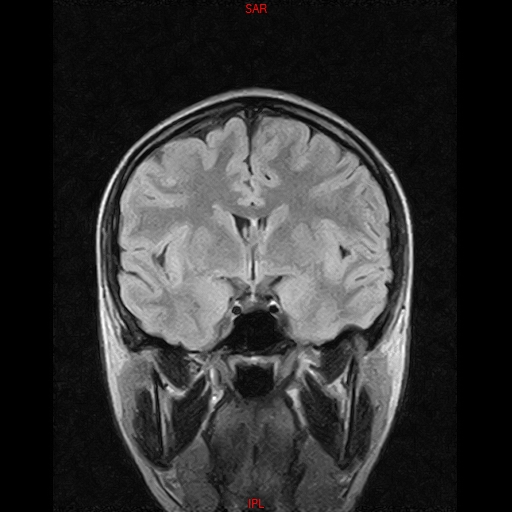

• RESONANCIA NORMAL CRANEAL T2 AXIAL

• RESONANCIA NORMAL CRANEAL FLAIR CORONAL

• RESONANCIA NORMAL CRANEAL T1 AXIAL